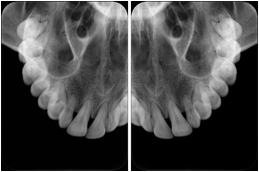

2 Occlusal Vertical Maxilla A Dental Image Layout

DL-C001A

Reference: DL-C001-U1L0

Reference: DL-C001-U2L0

00

Occlusal

18, 17, 16, 15, 14, 13, 12, 11, 13, 12, 11

01

21, 22, 23, 24, 25, 26,27, 28